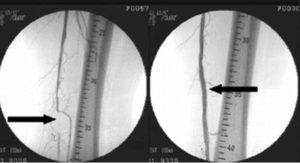

Самыми распространенными методами лечения при атеросклерозе сосудов ног являются эндоваскулярные методы – стентирование артерий, баллонная дилятация, ангиопластика. Они позволяют восстановить нормальную циркуляцию крови по сосуду без оперативного вмешательства.

Проводят такие процедуры в рентгеноперационной, на специальном оборудовании. По окончании на ногу пациента накладывают давящую повязку, и в течение 12–18 часов он должен соблюдать постельный режим.